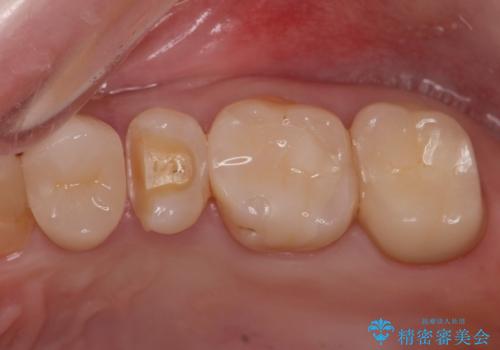

- 銀歯を無くしたいとの事で来院。

拡大鏡下でメタルを除去し虫歯がないことを確認してから白い詰め物、被せ物で治療を行いました。

適合の良い詰め物、被せ物が入りました。